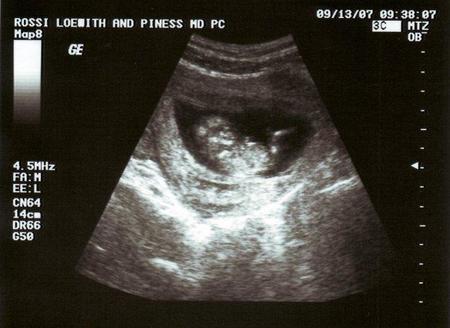

En las primeras entradas sobre el ejercicio físico de este especial sobre belleza en el embarazo os hablábamos de como el ejercicio no debía restringirse en el embarazo ya que es beneficioso para el mismo y también que se podían realizar ejercicios de tonificación y elasticidad para mejorar el parto.

En esta nueva entrada vamos a hacer un especial sobre el ejercicio cardiovascular durante el embarazo, aunque si bien hemos dejado claro que el ejercicio cardiovascular es recomendado durante el embarazo, es importante que se consulte siempre con el medico si el ejercicio que quieres realizar es compatible con tu estado.